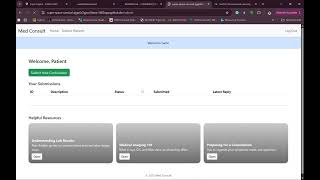

Med Consult by Badr Abdulmohsin Alsayed

Med Consult is a secure two-portal web platform that allows patients to submit medical consultations with uploaded reports and enables physicians to respond efficiently, ensuring streamlined communication, proper documentation, and HIPAA-compliant data protection